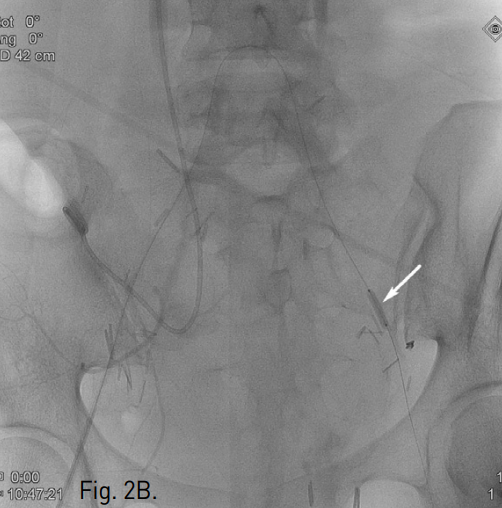

A. Pelvic angiogram shows a ruptured pseudoaneurysm (arrow) at perforation site of the left external iliac artery.